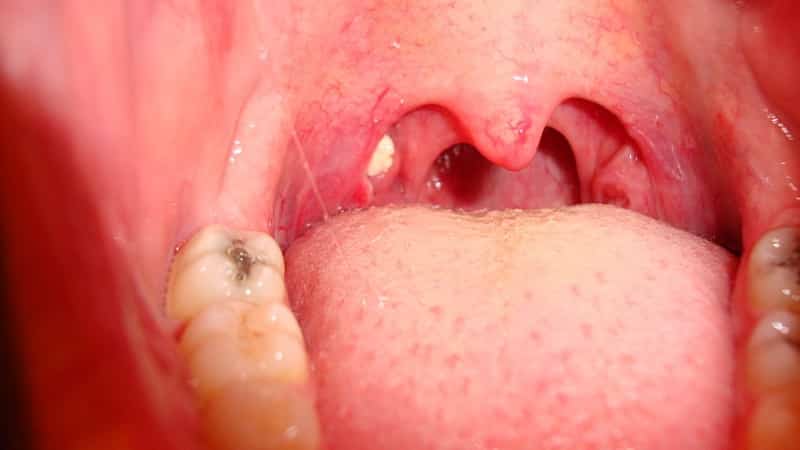

Обратите внимание на изображения выделений:

В это время у пациента появляются белые образования, обладающие неприятным запахом и необычным цветом. Кроме того, больные могут жаловаться на повышение температуры, болезненные ощущения в горле, покраснение слизистой и признаки общей интоксикации.

Белые комки могут вылетать из горла при кашле, чихании, пении или громком разговоре. По своей консистенции они могут быть плотными, упругими или мягкими. Степень их плотности зависит от времени, проведенного в горле, а также от этого фактора зависит и цвет выделений.